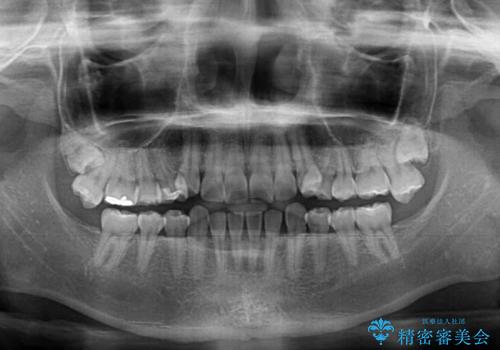

口腔内の状況を確認したところ、左右ともに下顎第二大臼歯が欠損しており、咬み合うべき上顎の第二大臼歯が著しく挺出していました。

挺出した大臼歯を元の位置に戻すことは現実的に難しいため抜歯することとし、補助装置とワイヤー装置により上顎歯列全体を後方に移動することとしました。